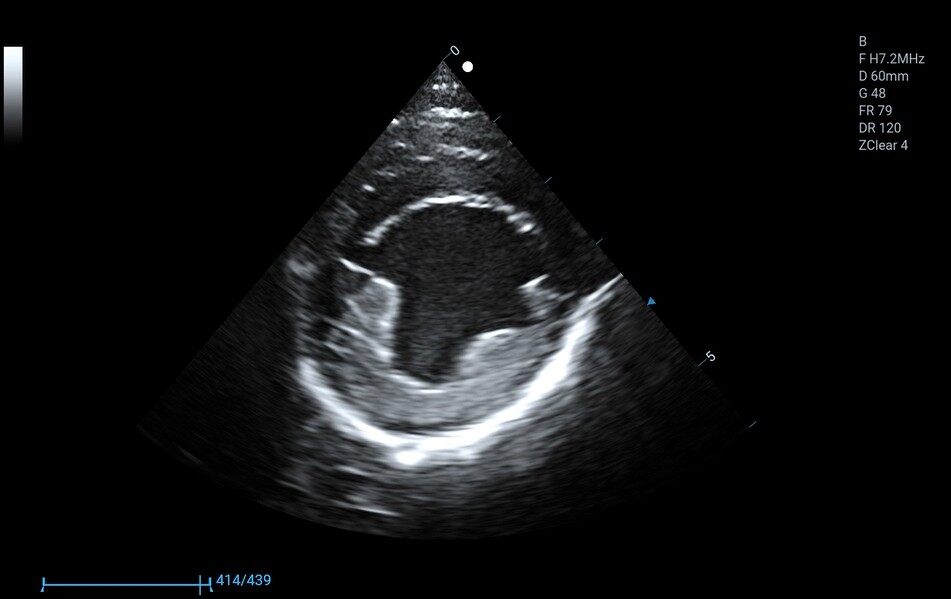

8P2MA ● 3.5-15.0MHz ● Single crystal phased array probe ● For Cardiology of felines |

3P2PA ● 1.0-6.5MHz ● Phased array probe ● For Cardiology of big-sized canines |

5P1PA ● 2.5-13.0MHz ● Phased array probe ● For Cardiology of small and medium-sized canines |